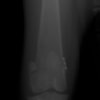

術前正面像

術後左後肢正面像

左後肢の挙上を主訴に来院されました。触診にて両関節の前方引き出し兆候、両膝蓋骨の内方脱臼を認めました。関節液検査より免疫介在性多発性関節炎は否定的でした。レントゲン検査にてfat pad signを伴う関節炎が認められたことから、前十字靭帯断裂と膝蓋骨内方脱臼(左GradeⅢ 右GradeⅢ〜IV)併発と診断し、手術を行いました。

手術は片足ずつ行い、両膝とも術中の関節鏡検査にて前十字靭帯の完全断裂と半月板損傷を確認しました。TPLO、半月板切除と滑車溝形成を始めとした膝蓋骨脱臼整復術を実施いたしました。膝蓋骨の安定化を測るために外側支帯を強固に縫合し、内側支帯は切除し縫合せずに開放状態にしています。

術前のTPAは左後肢33.1°右後肢26.8°でしたがTPLO実施により左後肢5.5°右後肢12°に矯正されました。